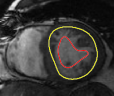

V-D Multiple Region Segmentation: Full Heart Segmentation

We now demonstrate our approach in performing challenging full heart segmentation: segmentation of the ventricles and epicardium all in one shot. Both the RV and epicardium are especially challenging as the contrast of the RV and background is subtle in comparison to the LV, and the myocardium wall near parts of the RV is very thin. We are not aware of another interactive method that is able to segment all structures, and so we compare to Medviso even though the method is not specifically tailored to the myocardium, but the method is generic and is able to propagate a segmentation. Further, Medviso does not segment multiple regions all at once and thus we perform separate segmentation of the LV, RV and epicardium. Since ground truth is not available for the outer wall of the myocardium in any standard dataset that we aware of, we show visual comparison.

Figure 10 shows the slice-wise results of our method and Medviso on a full 3D cardiac MRI sequence for a full cardiac cycle. Results indicate that our method is more accurate in capturing the shape of the ventricles and epicardium, and our method is especially more promising on the RV and epicardium. Figure 11 shows visualization of the results in 3D, and that our method more accurately resembles the structure of the heart.